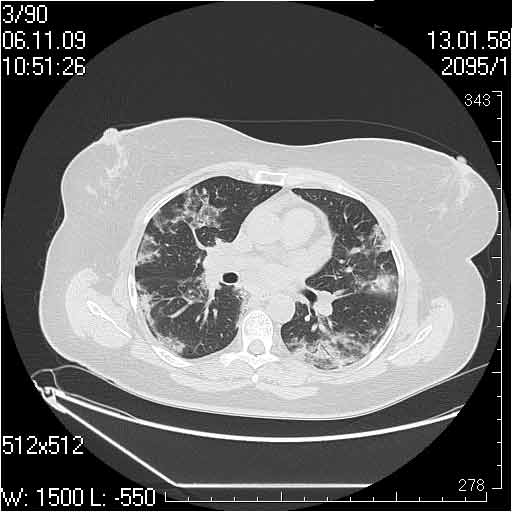

Случай №2

Мужчина 54 лет

Случай 2: картина патологических изменения довольно типична: GGOs & thickened interlobular septas = "crazy paving" sign. Наличие плотностей по типу матового стекла в сочетании с утолщением междолевых перегородок, даёт признак булыжной мостовой; на первом месте будет стоят диагноз альвеолярных протеиноз.